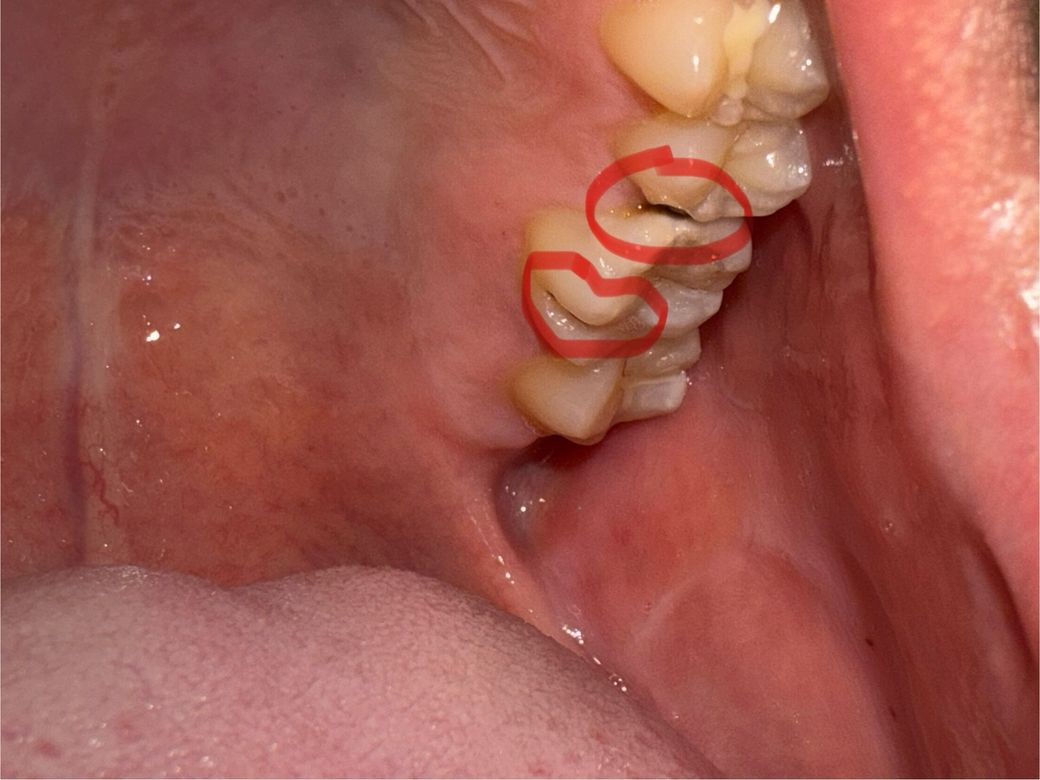

최근에 이가 조금 시큰거려서 사진을 찍어봤더니 충치가 생긴것 같습니다. 상태가 어떤지, 어떤 치료를 필요로 하는지 알고 싶습니다. 현지는 치과 치료가 너무 비싸서 어떤 치료를 필요로 하는지에 따라 잠시 귀국해서 치료 받고자 합니다ㅠㅠ 부탁드립니다!!

충치가 많이 진행된 상태 같습니다. 엑스레이를 찍어보고 나서 신경치료 또는 발치를 해야될 가능성이 높아 보입니다.

충치도 있고 치석도 있어보입니다

충치치료 받고 스케일링 받으세요

충치치료가 신경치료까지 이어질지 아니면 단순히 떼우는 치료로 끝날지는 엑스레이 찍어봐야 합니다